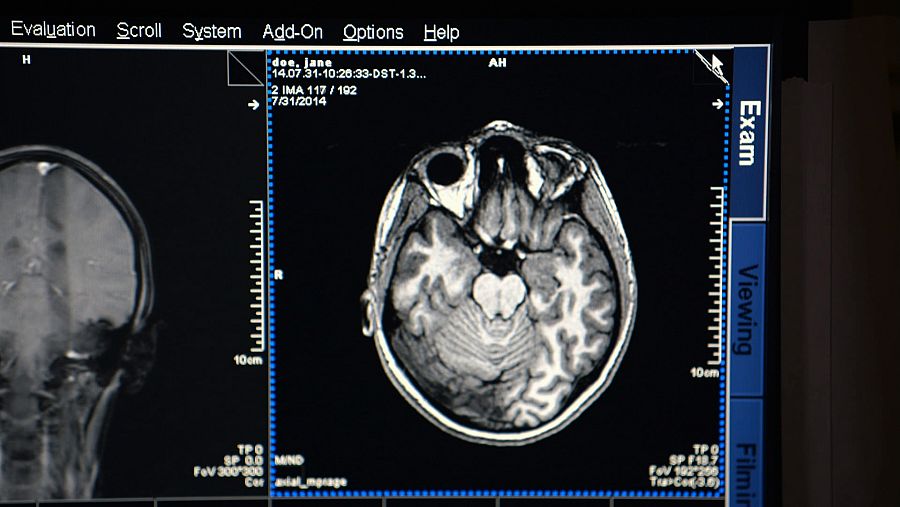

Para entender en qué punto falla el cerebro bipolar, hay que trazar un mapa del cerebro... o mejor dicho, varios mapas del cerebro que cartografíen el viaje de vuelta de la enfermedad mental a la salud mental.

Existen nuevos enfoques que permiten además la aplicación de otras terapias

Aunque la imagen por resonancia magnética funcional sigue siendo la herramienta cartográfica más usada, existen nuevos enfoques que permiten además la aplicación de otras terapias. La optogenética es la combinación de métodos ópticos y genéticos que ofrece una interpretación de los circuitos eléctricos del cerebro interviniendo en la actividad de las neuronas. La optogenética, probada en ratones, nos brinda la capacidad de cambiar lo que ocurre en el cerebro y de ver así en detalle los efectos resultantes y los mecanismos del cambio.